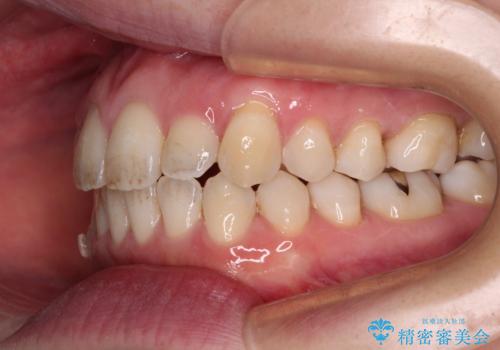

- 受け口傾向でクロスバイトの前歯を治したいとのことで来院された患者様です。

下顎骨が若干左側に変位していたため、右側にアンカースクリューを使用し、積極的に移動させながらインビザラインにて矯正治療を行うこととしました。

インビザラインによる矯正治療は、受け口傾向の治療に非常に適した方法であり、事前にシミュレーションに沿って治療を進めることできます。

今回の治療では骨格的な偏位があったためアンカースクリューを使用し、より確率の高い治療を行うことができました。